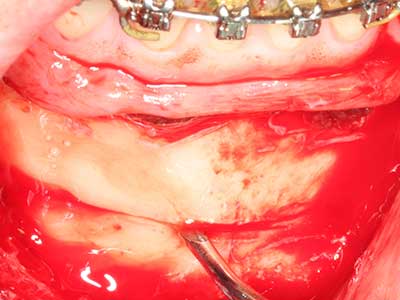

Die Präparation des lateralen Fensters bei der externen Sinusbodenelevation stellt gerade für chirurgisch unerfahrene Implantologen eine große Herausforderung dar. Die knöcherne Bedeckung der Kieferhöhle ohne eine Verletzung der darunterliegenden Schneider’schen Membran abzutragen ist dabei nur ein Teil der Operation – nach Schaffung eines ausreichenden Zugangs muss die Kieferhöhlenschleimhaut vorsichtig mobilisiert werden, um Raum für das einzubringende Material bzw. die Implantate zu schaffen. In dieser Indikation ist die Piezochirurgie zweierlei hilfreich: zum einen kann durch Verwendung diamantierter Instrumente eine selektive Knochenabtragung erfolgen und die darunter liegende Schleimhaut bleibt bei vorsichtiger Vorgehensweise intakt. Zum anderen unterstützen die Ultraschallfrequenzen zusätzlich eine komplikationslose Ablösung der Schleimhaut – sie werden durch spezielle stumpfe Ansätze in den Spaltraum zwischen Schleimhaut und Kieferhöhlenboden übertragen (Cassetta, Ricci et al. 2012, Pereira, Gealh et al. 2014) (Rickert, Vissink et al. 2013). So erscheint es nicht verwunderlich, dass in aktuellen Übersichtsarbeiten über die externe Sinusbodenelevation neben der Verwendung von rauen Implantatoberflächen und dem Einsatz von Knochenersatzmaterialien auch der Einsatz von piezoelektronischen Geräten als positiv bewertet wird (Wallace, Tarnow et al. 2012).

Bei der Knochenblockentnahme zeigen sich weitere Vorteile für die Piezochirurgie: Neben der bereits beschriebenen hohen Präzision bei der Osteotomie stellt sich gerade die Verwendung der dünnen Sägespitzen als besonders materialschonend heraus. Bei der Verwendung insbesondere von Lindemannfräsen sind mit deutlich höheren Entnahmeverlusten durch die dickere Instrumentenspitze zu rechnen (Lakshmiganthan, Gokulanathan et al. 2012). Die insbesondere bei retromolar entnommenen Blocktransplantaten notwendige basale Abtrennung wird durch speziell hierfür vorgesehene rechtwinklige Sägen erleichtert, so dass die Piezochirurgie als präzises, übersichtliches und sicheres Verfahren zur retromolaren Knochenblockgewinnung angesehen wird (Happe 2007) (Abb. 1-12).